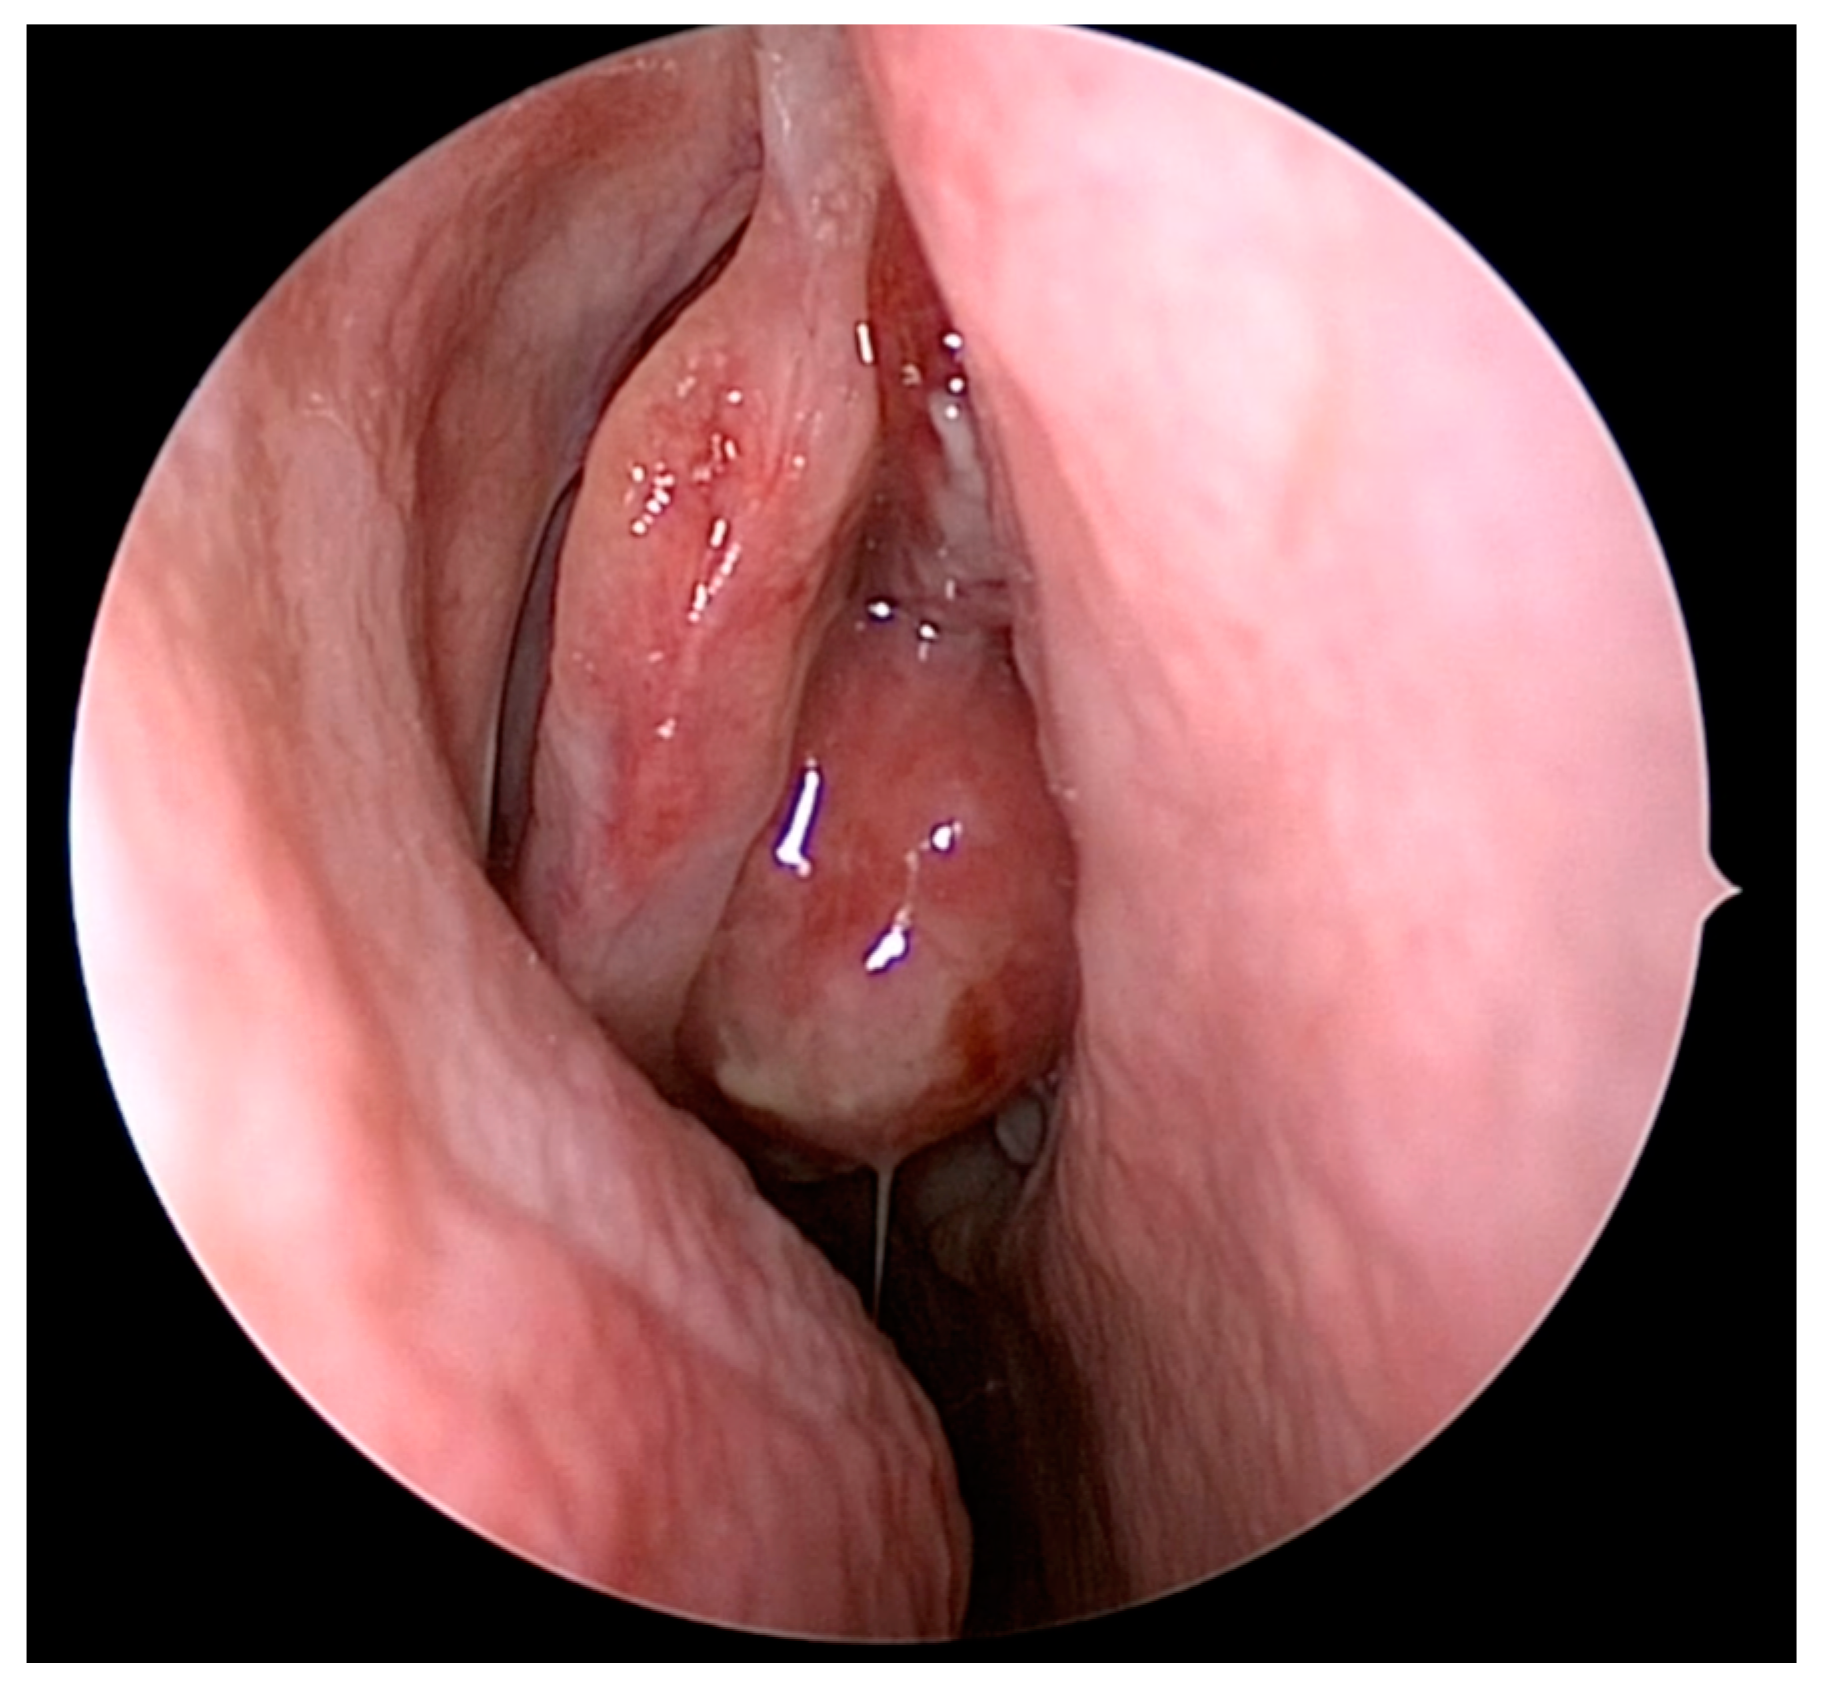

4. Olfactory Preservation and Surgical Resection of ONB

- Tajudeen, B.A.; Adappa, N.D.; Kuan, E.C.; Schwartz, J.S.; Suh, J.D.; Wang, M.B.; Palmer, J.N. Smell preservation following endoscopic unilateral resection of esthesioneuroblastoma: A multi-institutional experience. Int. Forum Allergy Rhinol. 2016, 6, 1047–1050. [Google Scholar] [CrossRef] [PubMed]

- Gompel, J.J.V.; Janus, J.R.; Hughes, J.D.; Stokken, J.K.; Moore, E.J.; Ryan, T.; Price, D.L.; Link, M.J. Esthesioneuroblastoma and Olfactory Preservation: Is it Reasonable to Attempt Smell Preservation? J. Neurol. Surg. B Skull Base 2018, 79, 184–188. [Google Scholar] [CrossRef] [PubMed]

- Nakagawa, T.; Kodama, S.; Kobayashi, M.; Sanuki, T.; Tanaka, S.; Hanai, N.; Hanazawa, T.; Monobe, H.; Yokoi, H.; Suzuki, M.; et al. Endoscopic endonasal management of esthesioneuroblastoma: A retrospective multicenter study. Auris Nasus Larynx 2018, 45, 281–285. [Google Scholar] [CrossRef] [PubMed]

- Gomez Galarce, M.; Yanez-Siller, J.C.; Carrau, R.L.; Montaser, A.; Lima, L.R.; Servian, D.; Otto, B.A.; Prevedello, D.M.; Naudy, C.A. Endonasal anatomy of the olfactory neural network: Surgical implications. Laryngoscope 2018, 128, 2473–2477. [Google Scholar] [CrossRef] [PubMed]